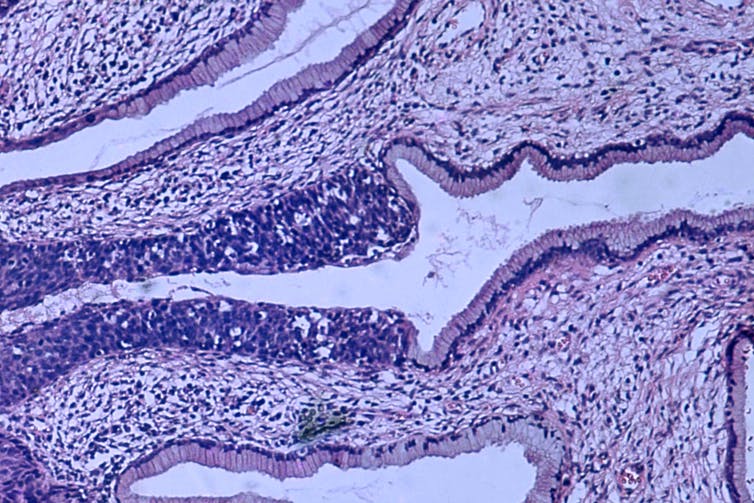

Imagen histopatológica de un carcinoma de cuello de útero en estadio 0. Foto: The Conversation Wimedia Commons Haymani